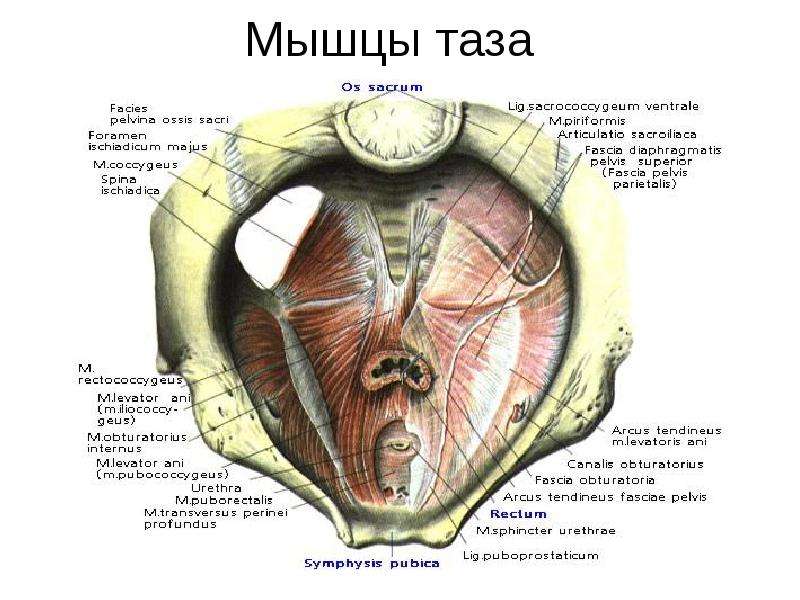

Анатомия малого таза: детальные схемы и изображения